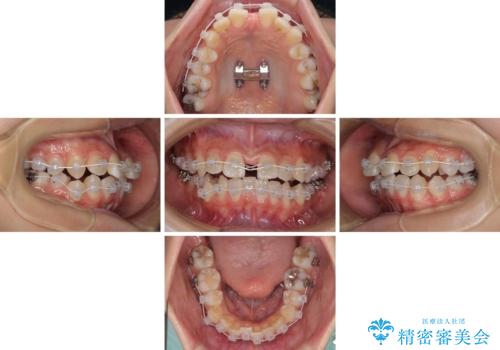

急速拡大装置を用いて上顎骨を側方に拡大し、上顎の叢生を解消するとともに下顎歯列拡大により下顎の叢生も解消することとしました。

急速拡大装置使用直後は著しいスペースが正中に発現するため、ワイヤー矯正を行いますが、今回は治療期間を短くしたいとのことで、上下全体をワイヤー装置にて矯正治療することとしました。